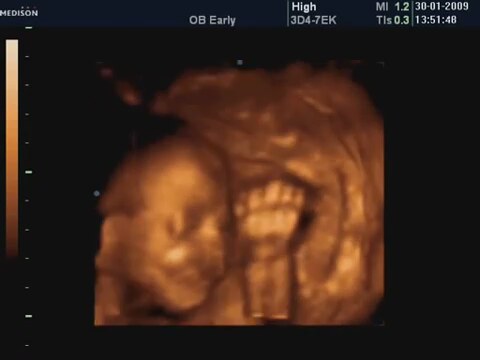

27 Haftalık Bebeğin 4 Boyutlu Ultrasın Görüntüsü